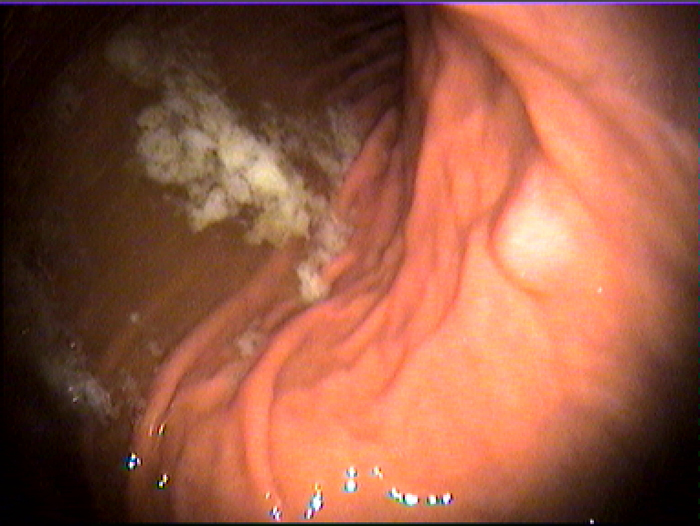

福州台江医院胃病诊疗科室医师指出,萎缩性胃炎是指胃黏膜表面反复受到损害后导致的黏膜固有腺体萎缩,甚至消失,黏膜肌层常见增厚的病理改变。